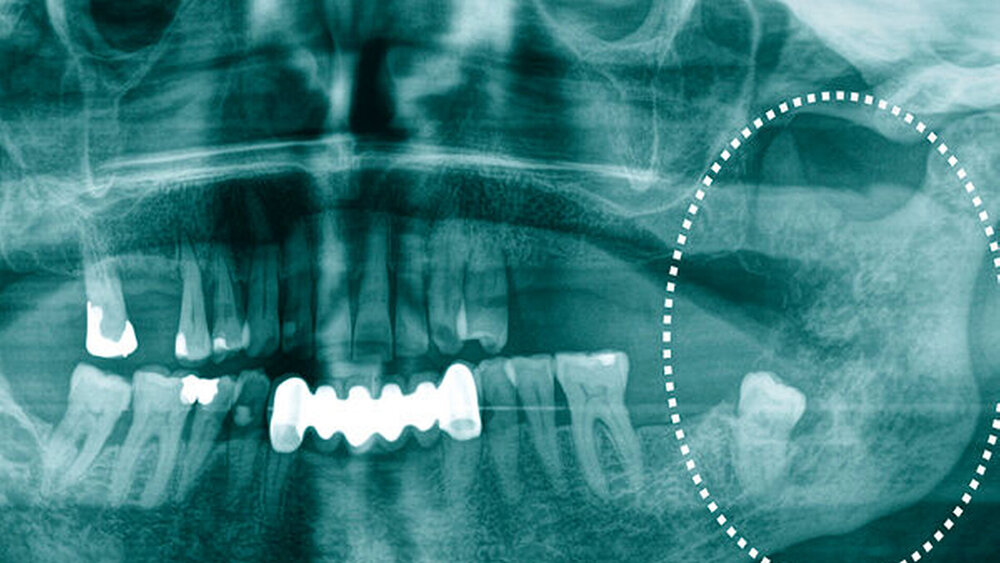

Die intraorale Untersuchung zeigte eine suspekte Mundschleimhautveränderung in regio 38. In der Panoramaschichtaufnahme zeigte sich ein tief verlagerter Zahn 38 mit einer hochsuspekten, inhomogenen und unscharf begrenzten, perikoronaren Osteolyse bis an die Incisura semilunaris des linken aufsteigenden Unterkieferastes (Abbildung 1).